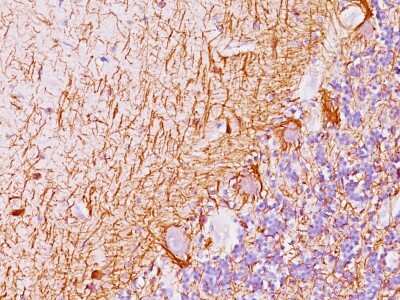

Immunohistochemistry-Paraffin: NF-H Antibody (NF421 + NFL/736) [NBP2-45288] - Human Cerebellum stained with Neurofilament Monoclonal Antibody (NF421 + NFL/736).

This MAb reacts with a 200kDa and 68kDa protein, identified as heavy and light sub-units of neurofilaments (NF-H & NF-L). Neurofilaments make up the main structural elements of axons and dendrites and are found in neurons, peripheral nerves, and sympathetic ganglion cells. Neurofilaments consist of three major subunits with molecular weights of 68kDa (NF-L), 160kDa (NF-M) and 200kDa (NF-H). Anti-neurofilament stains a number of neural, neuroendocrine, and endocrine tumors. Neuromas, ganglioneuromas, gangliogliomas, ganglioneuroblastomas, and neuroblastomas stain positively for anti-neurofilament. Neurofilaments are also present in paragangliomas as well as adrenal and extra-adrenal pheochromocytomas. Carcinoids, neuroendocrine carcinomas of the skin, and oat cell carcinomas of the lung also express neurofilament.